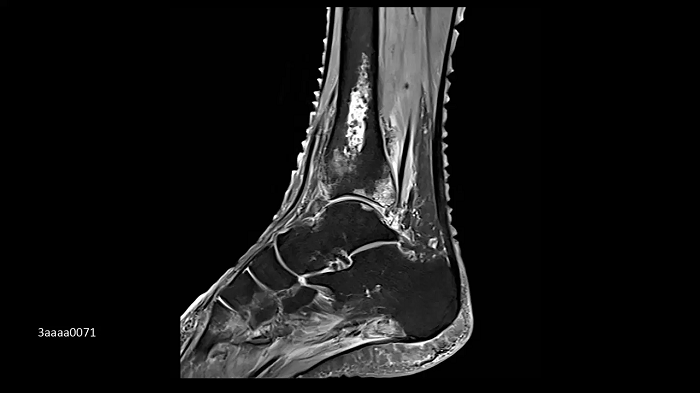

Foot/ankle imaging with the new Ultraflex Coils

The new coils allow ultra-high-density orthopedic imaging with the flexibility to apply in different anatomical regions.

Image Credit: Radiologie München Harlaching, Munich, Germany